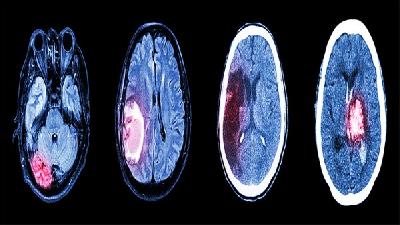

脑部对于我们来说是非常重要的部位,但是偏偏也容易出现各种各样的问题,比如动脉瘤,动脉瘤这种疾病就比较容易出现在我们的脑部,那么到底动脉瘤怎么治疗好呢?接下来我们就一起来具体的看看文章的介绍吧。介入治疗治疗脑动脉瘤:血管内弹簧圈栓塞术GDC是一种由钛合金制成的柔软的金属螺旋线圈。首先在腹股沟部位做一小切口,在股动脉插入一根导管,沿着血管一直延伸到脑动脉瘤的部位...